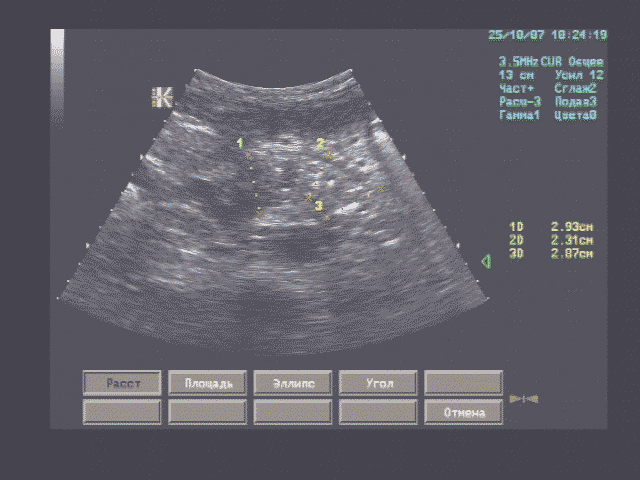

Печень - границы печени не расширены: нижний край правой доли у рёберной дуги, незначительно закруглён, переднезадний размер правой доли 119 мм, косой вертикальный 148 мм, переднезадний размер левой доли 59 мм, вертикальный 93 мм; контуры ровные, диафрагмальный контур нечёткий, паренхима неоднородная за счет гипоэхогенного участка вблизи правой боковой стенки желчного пузыря, имеющего округлую форму, диаметром 15 мм, имеющего ровные, относительно четкие контуры, однородное внутреннее строение; на остальном протяжении паренхима однородная, эхоструктура диффузно повышенной эхогенности рисунок зернистости нечёткий; внутрипечёночные жёлчные протоки не расширены, свободны, сосудистый рисунок обеднен.

Эхографические признаки хронического гепатита, гипоэхогенного очага 5 сегмента печени.